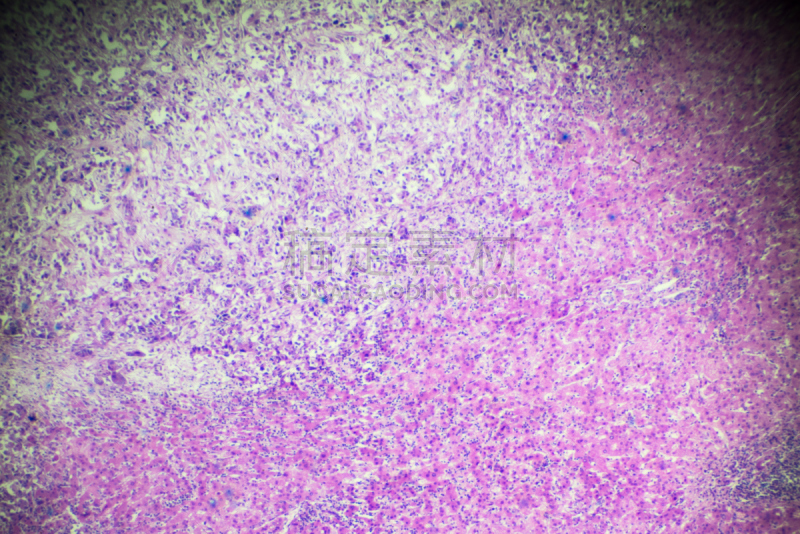

详情

JPG